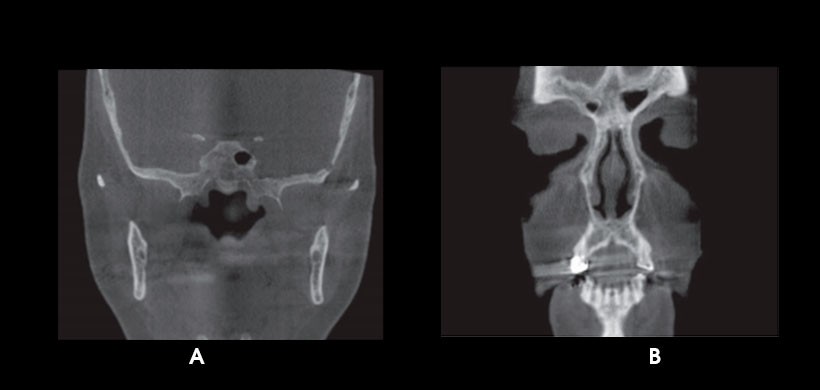

Fig 4. CBCT. A) Antrolito en seno maxilar izquierdo. B) Lesión quística en seno maxilar derecho.